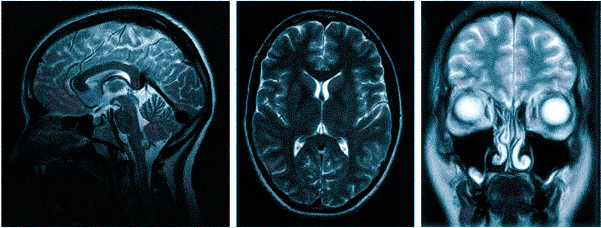

МРТ при головных болях (в трех проекциях): специальная программа выстраивает объемные изображения полученных срезов, что позволяет увидеть даже мельчайшие изменения и отдифференцировать патологию от нормы